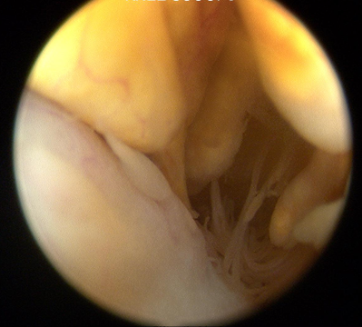

A diagnostic knee arthroscopy and biopsy was performed. This is the arthroscopic view during arthroscopy.

Q. What is your diagnosis?

Diagnosis: Pigmented villonodular synovitis

Pigmented villonodular synovitis (PVNS) is a rare benign proliferative condition affecting synovial membranes of joints, bursae or tendons, resulting from possibly neoplastic synovial proliferation with villous and nodular projections and haemosiderin deposition. PVNS is most commonly mono articular (80% knee joint) but occasionally it can be oligo articular [1].